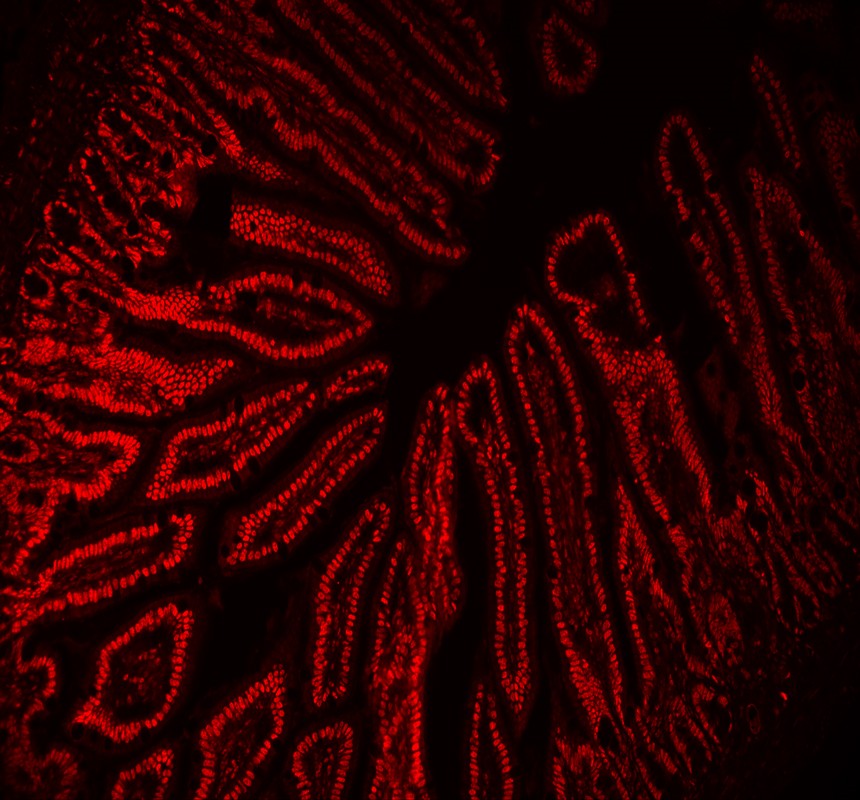

IF analysis of p68/DDX5 using anti-p68/DDX5 antibody (M00670-1).

p68/DDX5 was detected in a paraffin-embedded section of mouse intestine tissue. Fluoro594-conjugated Anti-mouse IgG Secondary Antibody (red)(Catalog#BA1141) was used as secondary antibody.